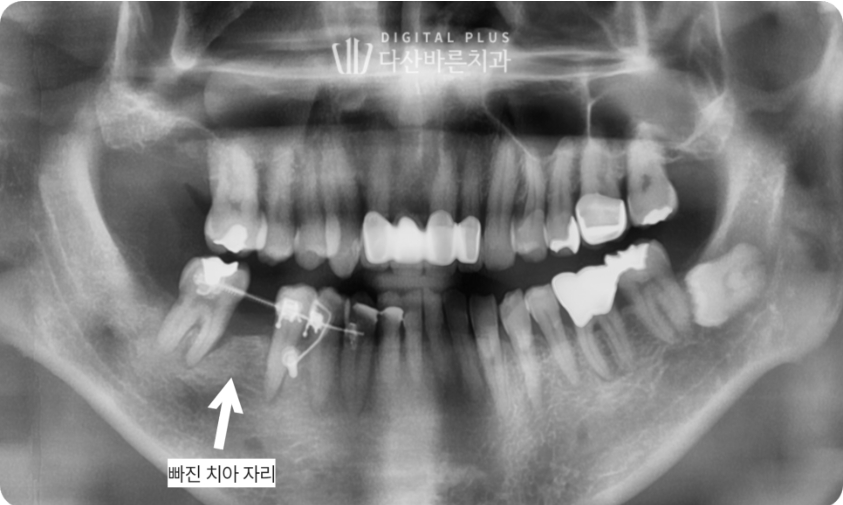

▲ 교정치료 시작 5개월 후 치아 배열이 정돈되고, 임플란트 심을 자리가 형성된 모습.

보통 연세가 있을수록 뼈가 딱딱하게 굳기 때문에 교정 시 치아 이동 속도가 느린데,

우리 환자분은 50대 연세에도 불구하고, 5개월 만에 임플란트 심을 수 있는 공간이 형성되었습니다.

그럼 그 형성된 공간에 임플란트를 심으면 치료가 완성됩니다.

▲ 교정으로 형성된 공간에 임플란트 식립 후 무너진 치아 배열과 교합을 회복한 모습.

자연치아의 불필요한 발치 없이, 교정을 통해

치아를 이동시켜 임플란트를 심어준 케이스입니다.

이렇게 치료해 주면, 무너졌던 교합이 다시 정상으로 회복되어

음식 씹기도 편하고, 치아 사이 음식물이 끼는 일도 줄어들게 됩니다.